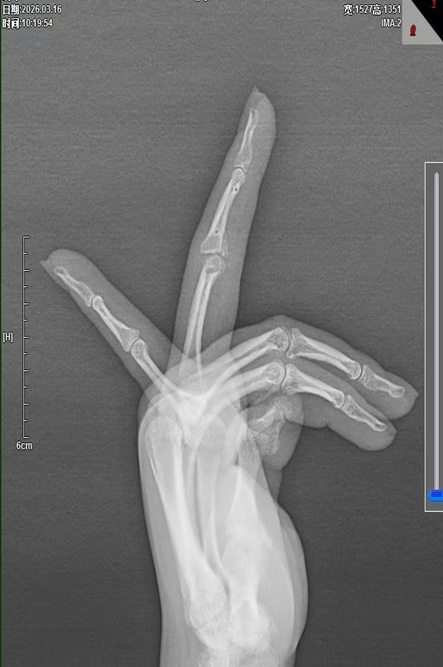

经过规范治疗与系统康复指导,患者手指PIP关节对位良好,僵硬症状快速缓解,手指屈伸幅度、抓握力量均得到明显提升,原本受限的日常生活功能全面恢复。患者对治疗效果高度认可,专程对骨科团队的精湛技术表示感谢。